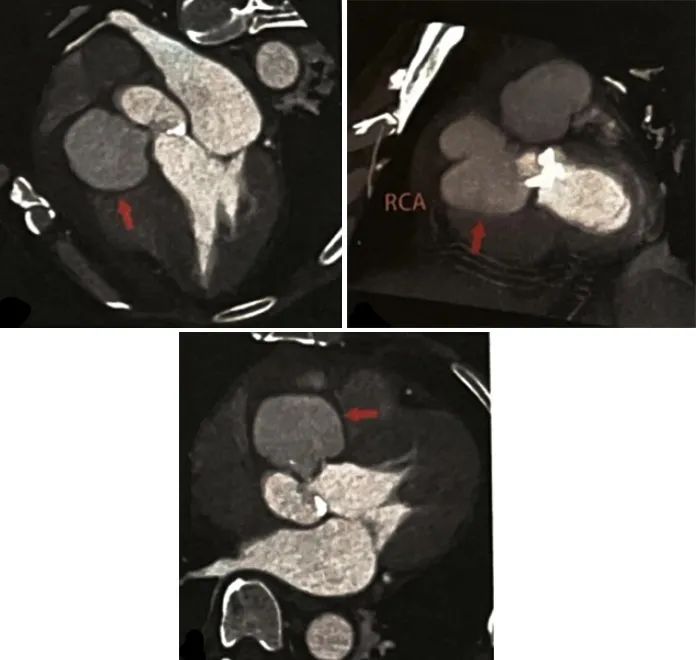

◇诊疗经过:患者入院第22天复查冠状动脉CTA示:右冠窦旁、右侧房室沟见巨大对比剂池,大小45 mmx46 mmx59 mm,较前明显增大,脓肿与主动脉窦部见3 mm的交通口。左主干、前降支、回旋支表现同前,右冠状动脉开口至中段受脓肿压迫而未见显影(图3)。

图3 患者发生心肌梗死后夏査冠状功脉 CTA结果

急性冠脉综合征是感染性心内膜炎的一种少见的并发症,已有文献报道感染性心内膜炎并发急性心肌梗死发生率仅1%~3%,其病因包括冠状动脉栓子栓塞、较大的赘生物阻塞了冠状动脉开口、瓣周脓肿压迫了冠状动脉、严重的主动脉关闭不全。该患者在等待进一步外科手术期间,突然发生了急性下壁ST段拾高型心肌梗死伴三度房室传导阻滞,考虑为急性感染性心内膜炎感染加重,右冠窦壁破溃,与主动脉根部脓腔相通,导致主动脉瓣周脓肿的压力增高和体积增大,右冠状动脉开口及近段水肿明显、受压迫闭塞,导致了急性下壁心肌梗死。

本病例通过两次冠状动脉CTA明确显示了主动脉窦脓肿的病变范围、形态、大小的变化,以及与主动脉窦、右心房、右冠状动脉的结构关系,明确了突发急性心肌梗死的原因,指导了手术方案的制订。该患者经外科手术治疗后病情好转出院,随访4年病情稳定,说明心脏CTA在感染性心内膜炎合并瓣周脓肿的诊断中有较好的临床应用价值。